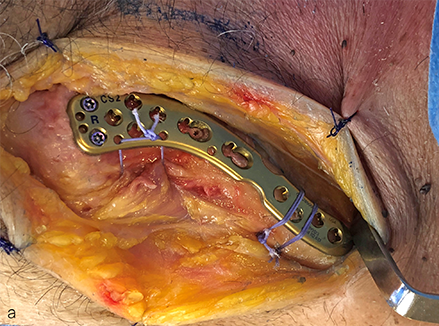

Open Reduction and Internal Fixation (ORIF)

This is the most common surgical method.

Procedure steps:

- Small incision over the collarbone

- Bone fragments repositioned

- Fixation using metal plate and screws

This stabilizes the bone and allows early functional recovery.

Dr. Senthilvelan personally performs all fracture surgeries and supervises the full recovery process.